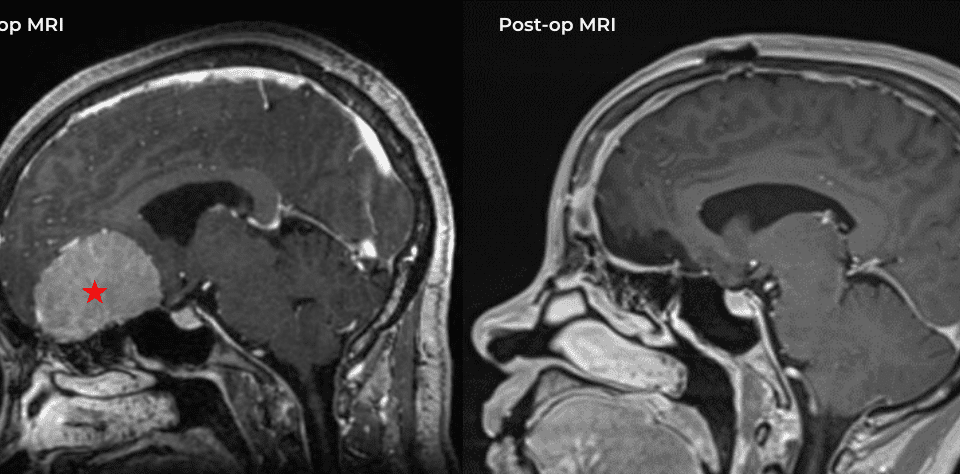

A young lady presented with a myriad of disabling difficulties, after a flourishing adolescence full of academic and athletic successes. Her headaches, located on the top […]